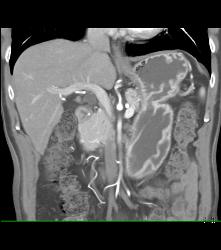

Antral Carcinoma